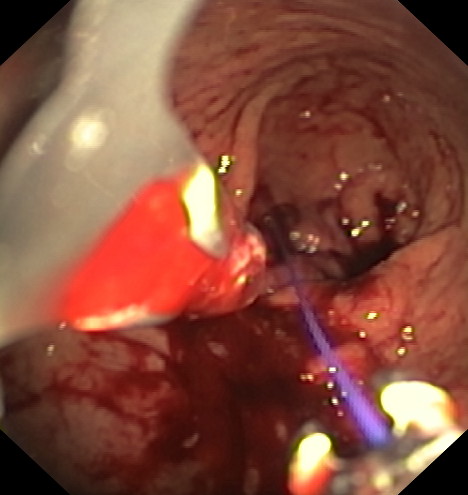

Mediante un sistema de sutura acoplado a un endoscopio, se sutura el estómago “desde dentro” dándole un aspecto similar al conseguido por la cirugía de gastrectomía vertical laparoscópica (manga gástrica quirúrgica), pero con menor riesgo quirúrgico y muy buenos resultados a medio y largo plazo. De esta manera se limita la cantidad de comida que puede entrar en el estómago e igualmente hace que la digestión sea más lenta, favoreciendo enormemente la saciedad y la pérdida de peso. Es una técnica definitiva, pero por vía oral, ni realizar heridas abdominales ni cicatrices.